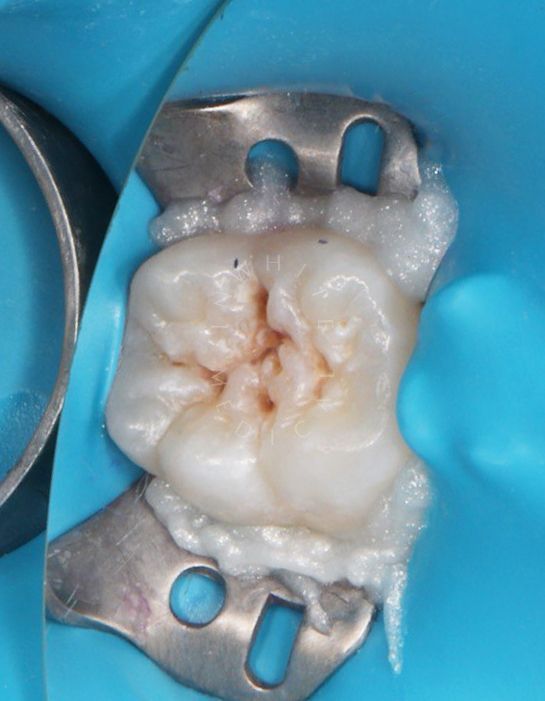

етская стоматология под наркозом Москва. Лечение молочных зубов и установка металлических коронок во сне - до процедуры